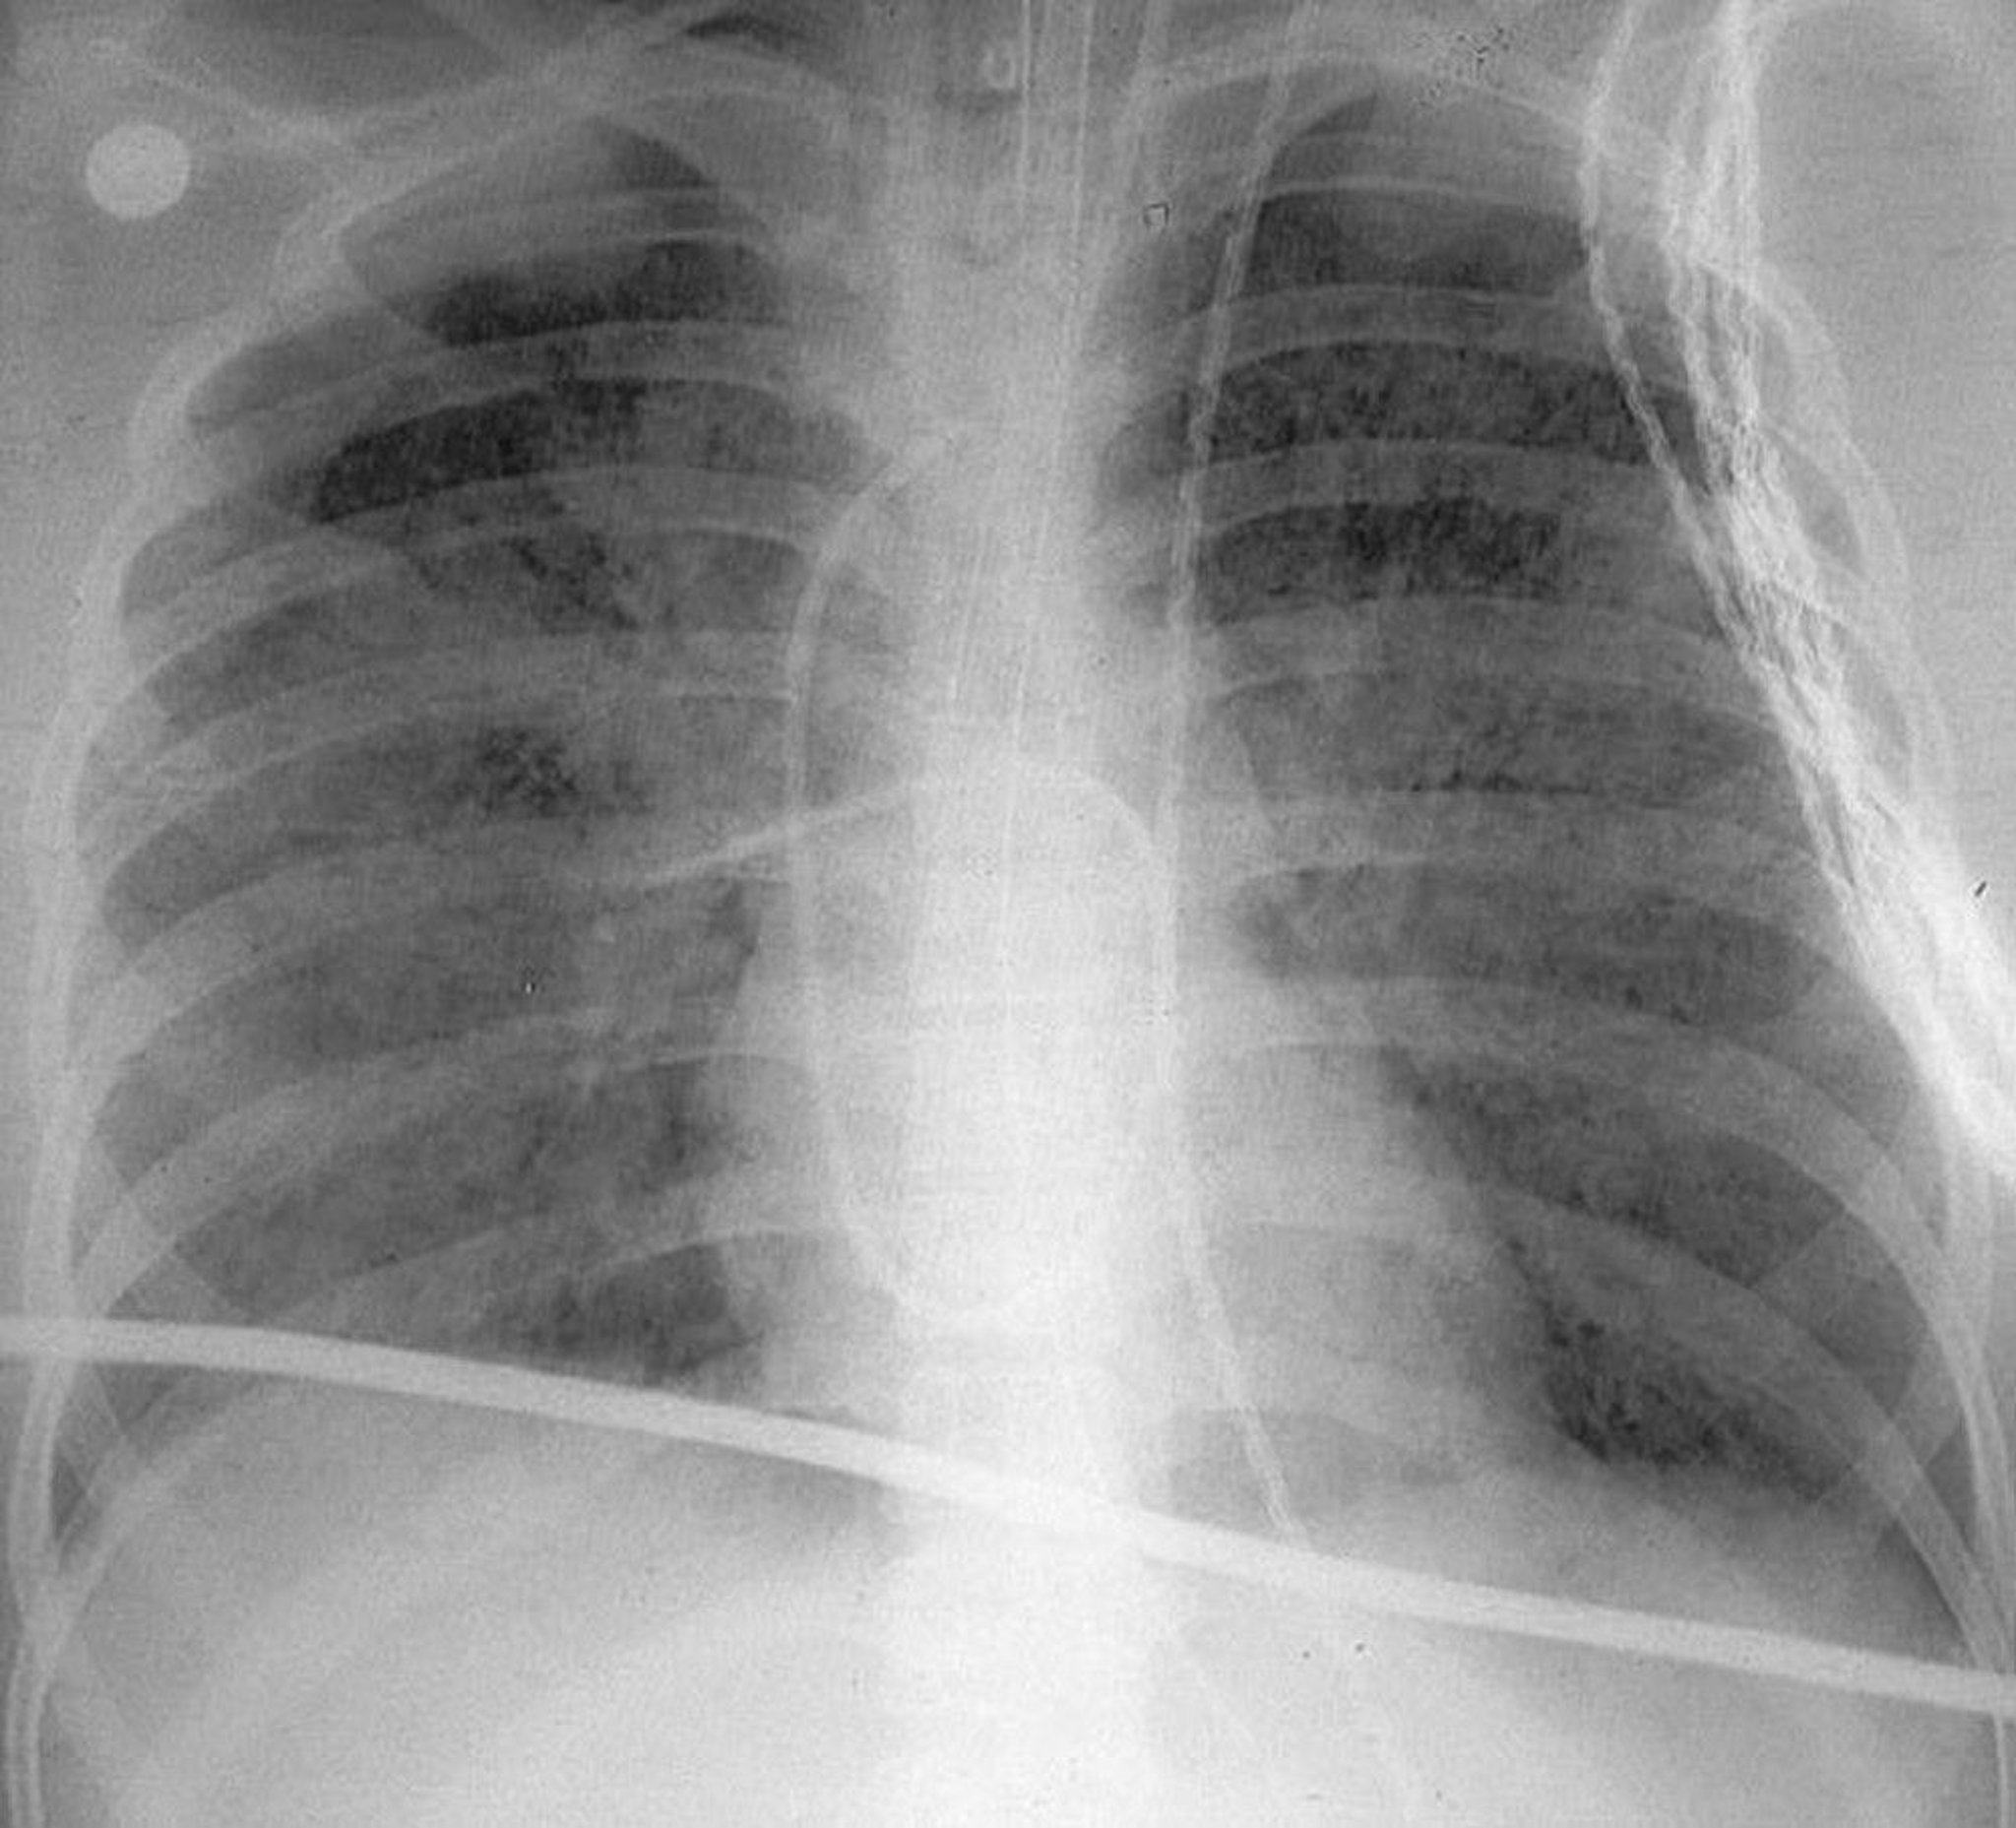

Acute Respiratory Distress Syndrome

This upright chest x-ray shows diffuse bilateral opacities characteristic of acute respiratory distress syndrome (ARDS).

By permission of the publisher. From Herdegen J, Bone R. In Atlas of Infectious Diseases: Pleuropulmonary and Bronchial Infections. Edited by G Mandell (series editor) and MS Simberkoff. Philadelphia, Current Medicine, 1996.